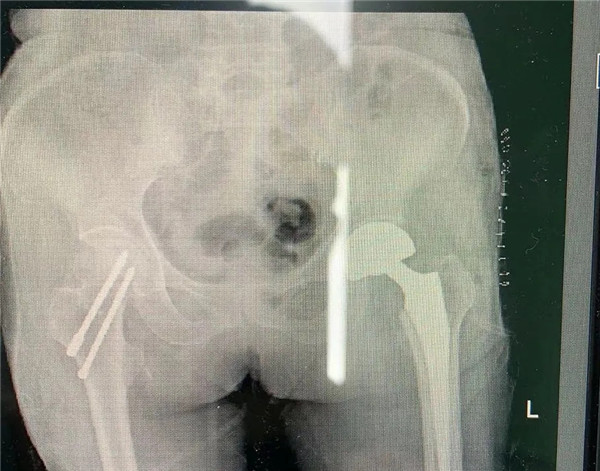

手術(shù)由危立軍副院長(zhǎng)主刀,用最少的時(shí)間完成人工關(guān)節(jié)置換,從劃刀到假體安裝好僅僅10分鐘。術(shù)后王老太太一天天好轉(zhuǎn)起來(lái),現(xiàn)已下地康復(fù)行走,臉上洋溢開(kāi)心的笑容。

確定手術(shù)后,經(jīng)內(nèi)科、麻醉科、超聲科等專(zhuān)家會(huì)診后,王老太太符合手術(shù)指征,3月5日,老太太接受了股骨頭置換手術(shù)。